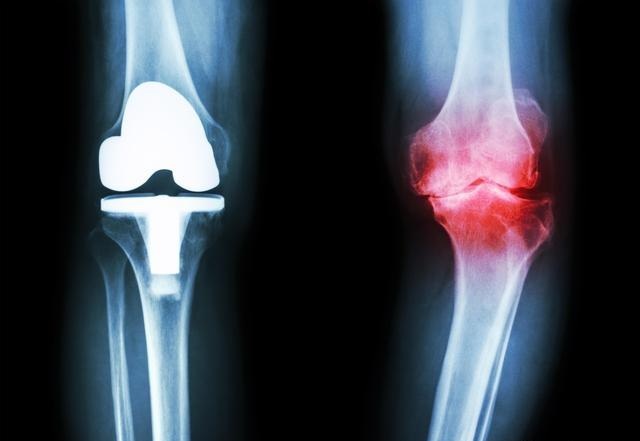

首先需要说明的一点就是,“骨质增生”“骨刺”这些其实都是老百姓由于不理解而对骨关节炎不规范的俗称!临床上是没有这两种疾病的,它们只是关节退变后的一种生理病理表现,一般会在X光片中报告,但基本很少出现在诊断里面。下面我就以临床上最常见的膝关节骨性关节炎来解释。

首先膝关节由三块骨头组成---股骨、胫骨、髌骨,三块骨头之间的关节面被一层关节软骨覆盖,就跟我们平时吃的“猪筒骨”一样,关节软骨像海绵软垫一样,起着吸收震荡,减压的作用。随着年纪的增长,关节软骨慢慢磨损,厚度也越来越薄。磨损下来的“碎屑”就很容易诱发关节炎的发生;最后,关节软骨部分磨损甚至全磨损完了,骨头磨骨头,就会出现剧烈的疼痛!

关节软骨这块“软垫”没有了之后,失去了软骨的防震减压功能,膝关节面受到的压力就会变大;人体是个神奇的生物体,为了保证膝关节在相同压力下或者更大的压力下保持压强不便,那么就只有增加受力面积了,骨头慢慢就开始增生了,“骨刺”就长出来了,长出来的骨刺,增加了膝关节的受力面积,因此可以在一定程度上保持膝关节压强波动不会过大。

因此,“骨质增生”“骨刺”这两个东西是人体自身的保护性产品,一般看大于60岁的老年人基本都会有,没有症状的话,不用老是想着去“治愈”它!